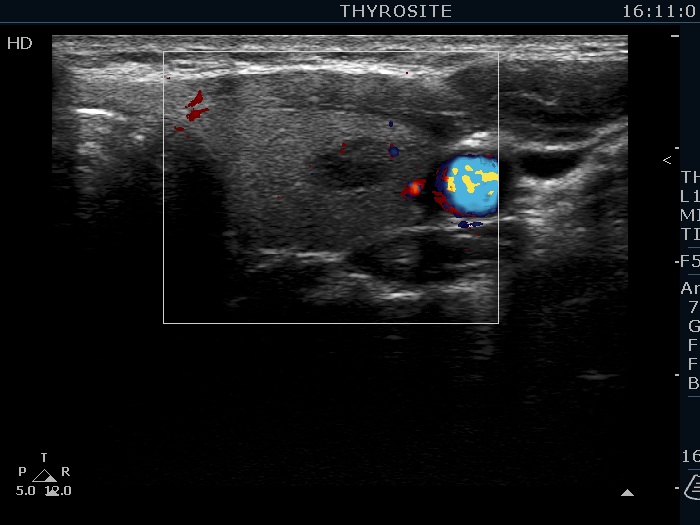

Lower part of the left lobe, transverse scan, color Doppler mode. This lesion shows a very scanty vascularity.